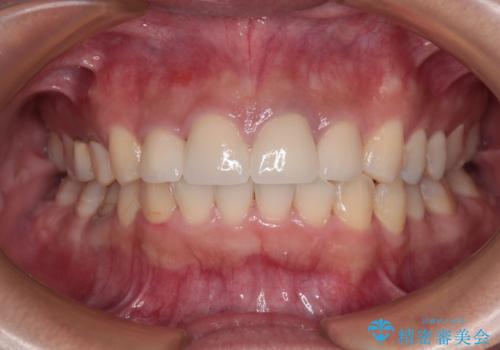

歯列から飛び出た歯 ワイヤー矯正で整った歯列に

歯列以外に、上顎左右側切歯が矮小歯であり、上顎4前歯は失活していたため、矯正治療で歯列を整えるとともに上顎前歯の幅を調整し、矯正治療後にオールセラミッククラウンにて審美歯科治療を行うこととしました。

下顎の小臼歯を移動しきるのに2年弱の期間を要することとなり、補綴治療も合わせて2年半ほどの治療期間となりました。

口元の印象が大きく改善し、患者様には大変満足していただけました。